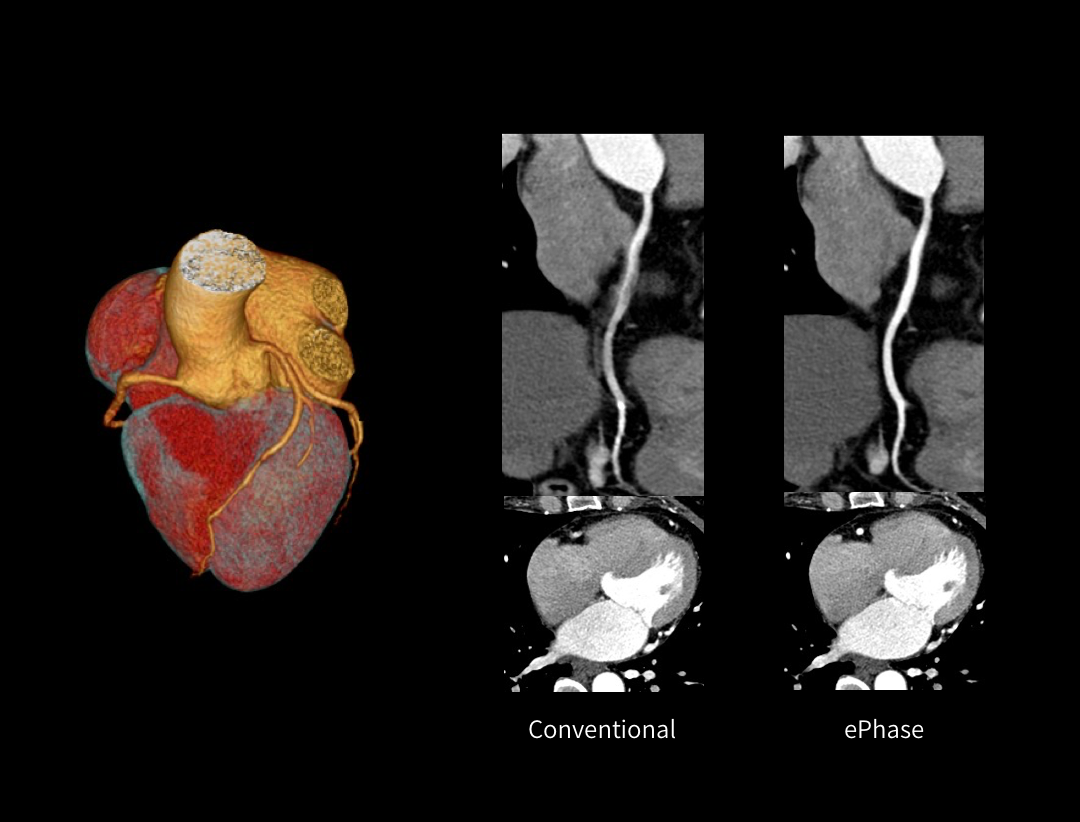

CardioXphase

最適位相の自動選択。

Aortic Dissection